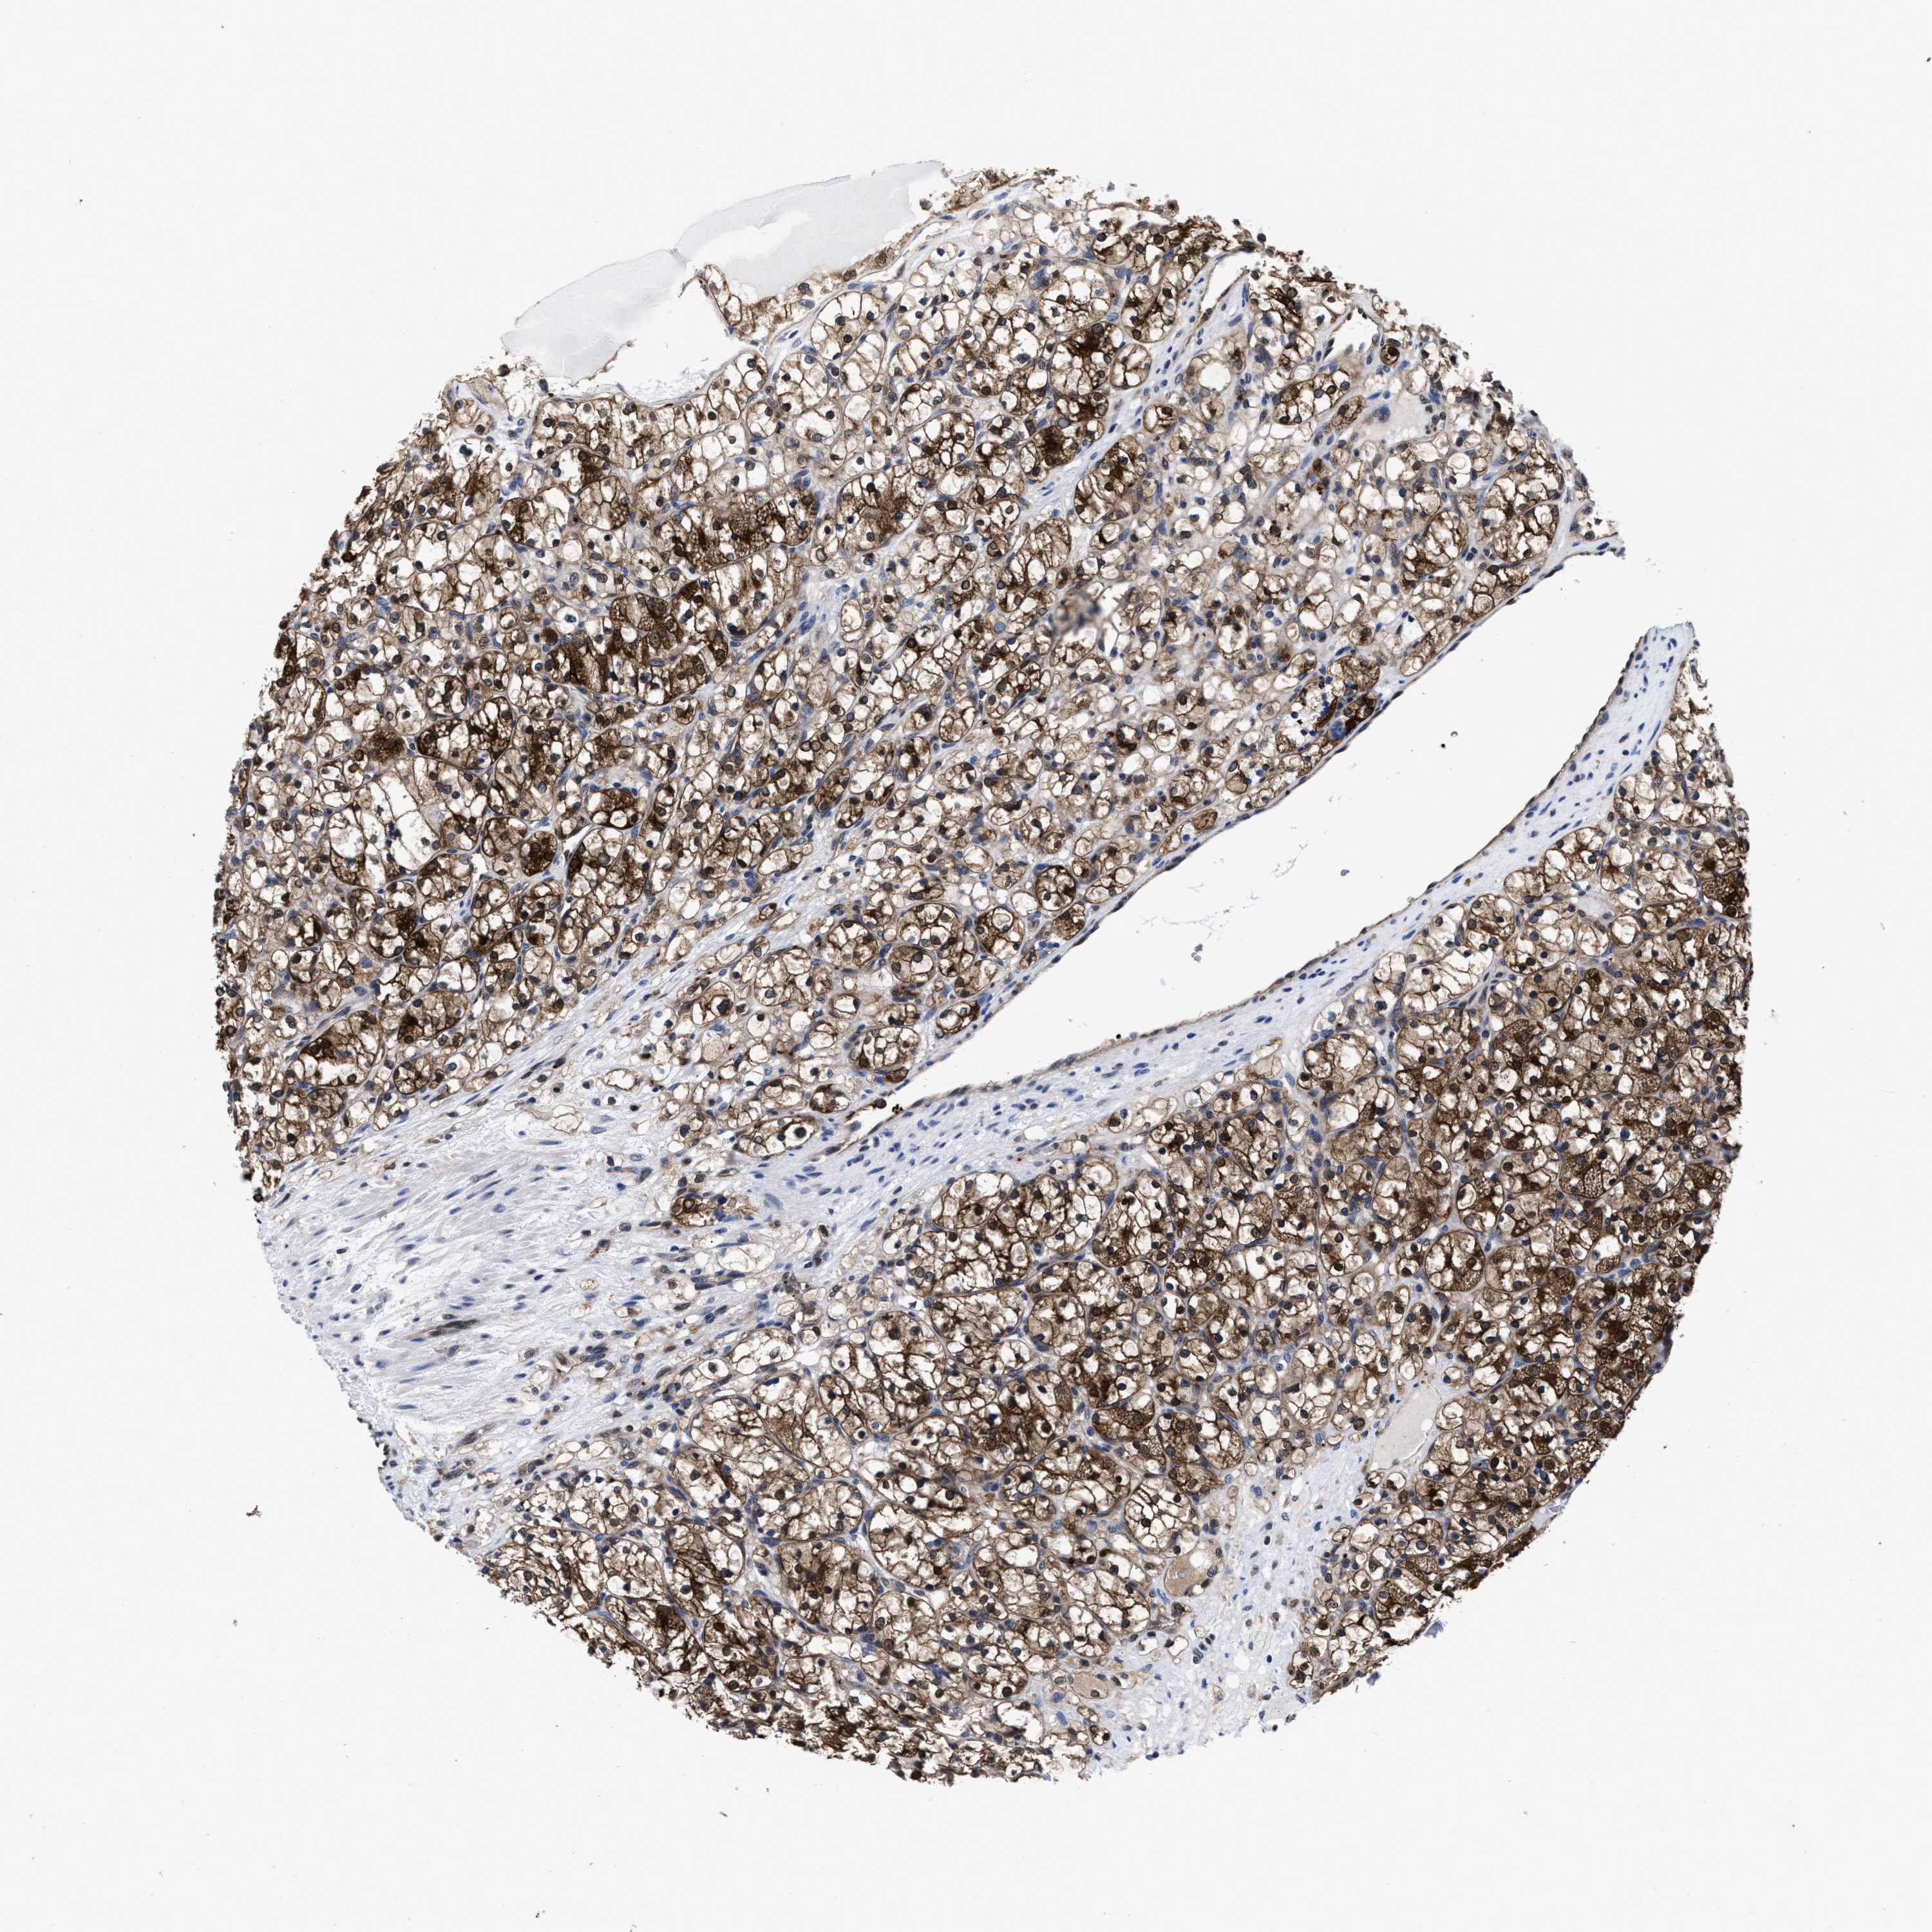

CANCER RENAL CANCER Show tissue menu

KICH TCGA KIRC TCGA KIRC VALIDATION KIRP TCGA PROTEIN RCC CPTAC PROTEIN EXPRESSION

ACLY is potential prognostic, high expression is favorable in Kidney Renal Clear Cell Carcinoma (TCGA)

ACLY is not prognostic in Kidney Renal Clear Cell Carcinoma (validation)